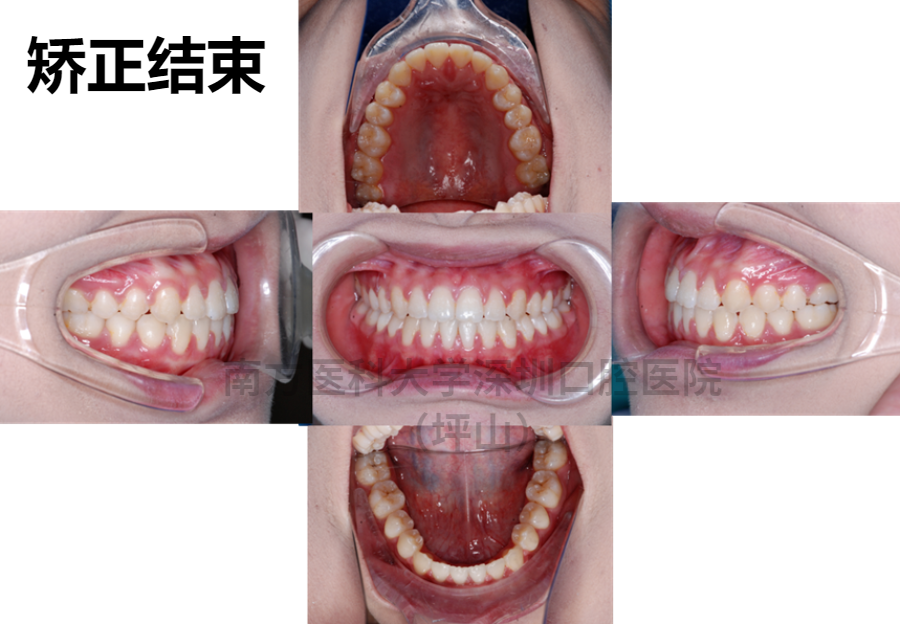

整完后,不仅脸正了,下巴的曲线也出来了,鼻子也更挺了,五官也变得立体起来,确实变美了很多。

一年多的时间,关闭了我的牙齿间隙,咬合关系也得到了改善。在整个正畸的过程中,易医生非常认真负责,人很温柔,超级耐心。

最后的结果就是,仅仅通过正畸,就达到了我预期的效果,让我超级满意!

我收获的不仅是牙齿整齐,侧脸也变得更加好看了,人也变得更加自信了,更爱笑也爱说话了。